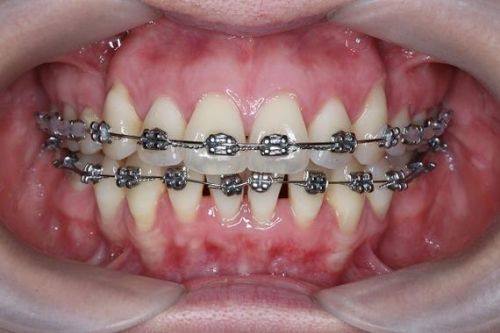

牙齿矫正:涵盖舌侧矫正、隐形矫正、金属自锁托槽矫正等多种技术,由经验多的正畸医师坐诊,可根据患者面部五官协调程度定制个性化方案,数字化模拟矫正成效,能解决牙列拥挤、龅牙、地包天等多种复杂正畸问题。

吴燕燕:执业医师,从事牙科诊疗工作10多年,拥有同济大学正畸学硕士学位,擅长舌侧矫正、隐形矫正、金属自锁托槽矫正、金属非自锁托槽矫正,曾在公办口腔医院执医多年,成功完成数千例牙齿矫正病例,是隐适美讲师、舌侧矫正明星医生。

杨广媛:主治医师,口腔正畸学硕士,擅长处理牙列拥挤、牙列稀疏、龅牙、牙齿不齐、下颌后缩等复杂口腔问题,精通舌侧矫正、颌面正畸、隐形矫正等技术,尤其擅长使用金属自锁托槽和陶瓷自锁托槽。

李华美:主治医师,擅长牙列拥挤、龅牙、地包天、牙齿不齐、下颌后缩等问题的矫正,精通牙齿早期矫治、乳牙间隙管理、隐形矫正、金属自锁托槽矫正、陶瓷自锁托槽矫正,专注提升患者口腔健康与牙齿美观度。